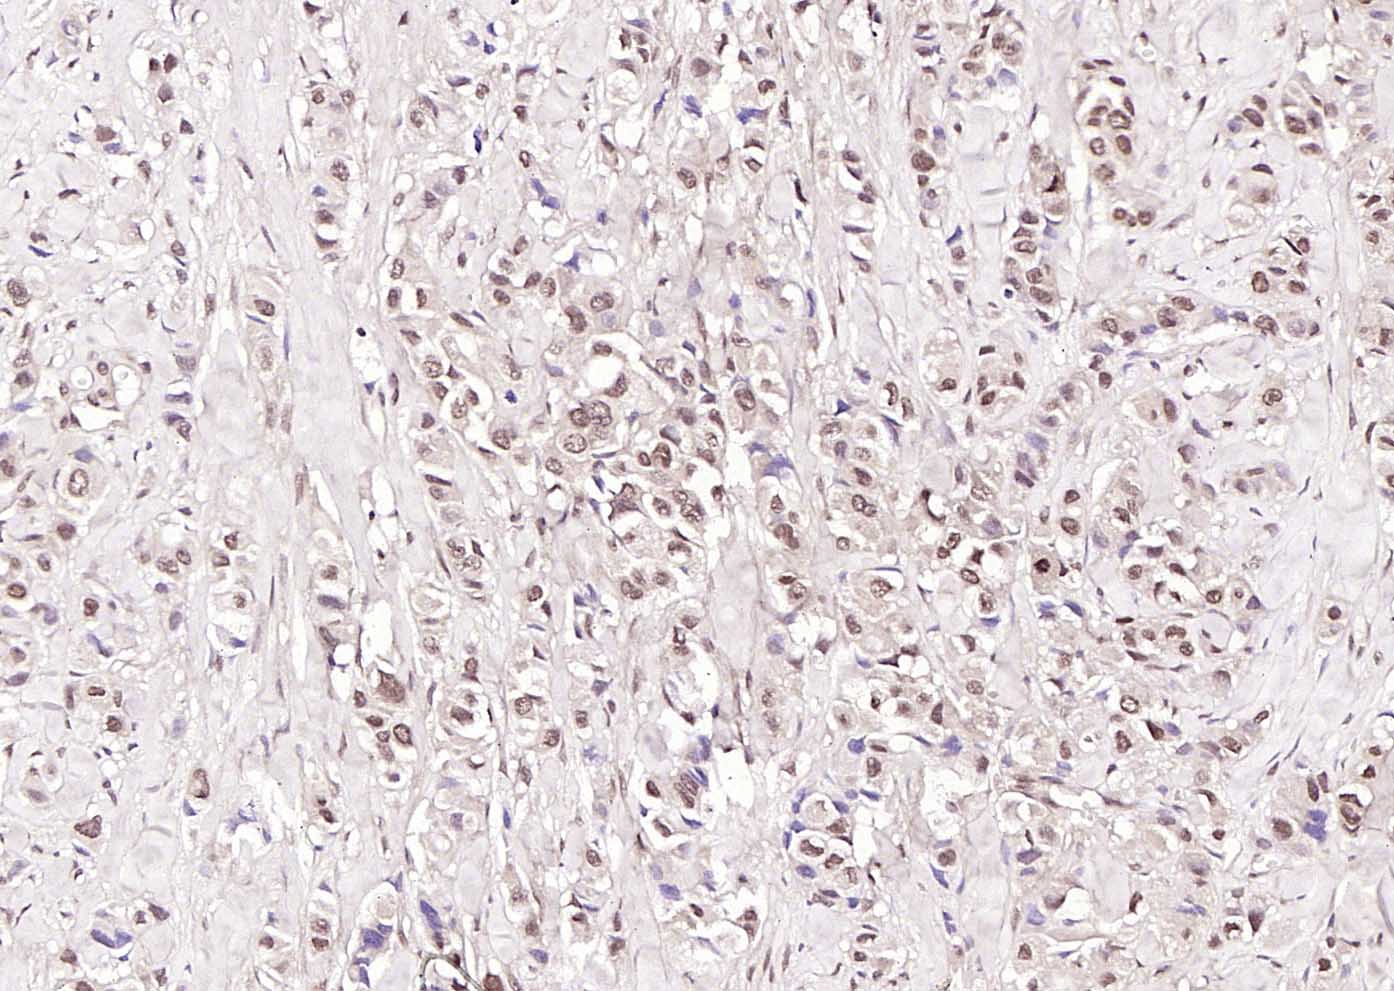

Paraformaldehyde-fixed, paraffin embedded (human breast carcinoma); Antigen retrieval by boiling in sodium citrate buffer (pH6.0) for 15min; Block endogenous peroxidase by 3% hydrogen peroxide for 20 minutes; Blocking buffer (normal goat serum) at 37°C for 30min; Incubation with (Phospho-cdc25A (Ser178) ) Polyclonal Antibody, Unconjugated (bs-3095R) at 1:200 overnight at 4°C, followed by operating according to SP Kit(Rabbit) (sp-0023) instructionsand DAB staining.